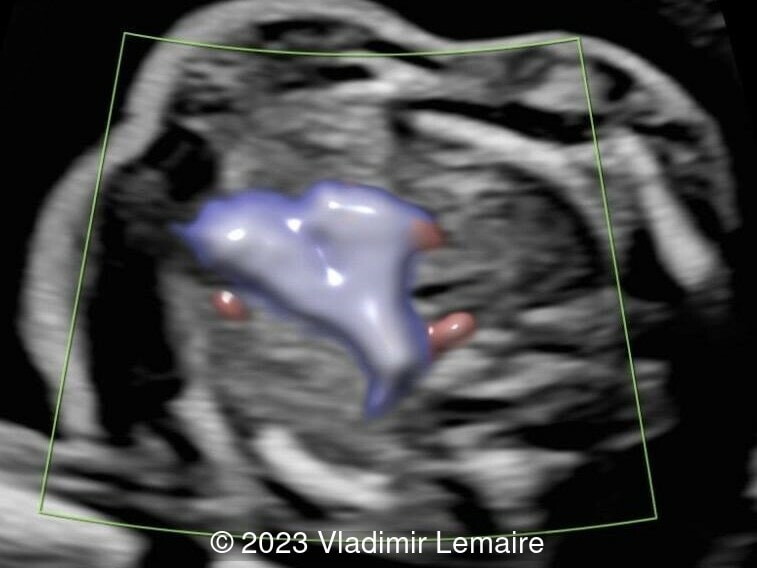

Aberrant right subclavian artery, seen in blue, in a fetus at 23 weeks of gestation.

Image 7 Aberrant right subclavian artery, seen in blue, in a fetus at 23 weeks of gestation.